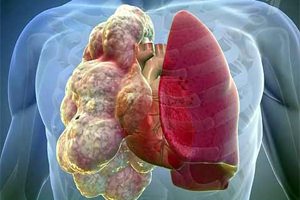

Эмфизема лёгких: причины, симптомы и лечение

Врачи отмечают, что эмфизема лёгких является серьёзным заболеванием, которое требует внимательного подхода к диагностике и лечению. Специалисты подчеркивают, что основными факторами риска являются курение, загрязнение воздуха и наследственная предрасположенность. При этом заболевание характеризуется разрушением альвеол, что приводит к снижению дыхательной функции и ухудшению качества жизни пациентов. Врачи рекомендуют раннюю диагностику, включая спирометрию и рентгенографию, для своевременного выявления проблемы. Лечение может включать медикаментозную терапию, реабилитацию и, в некоторых случаях, хирургическое вмешательство. Важно также акцентировать внимание на изменении образа жизни, включая отказ от курения и регулярные физические нагрузки, что может значительно улучшить состояние пациентов.